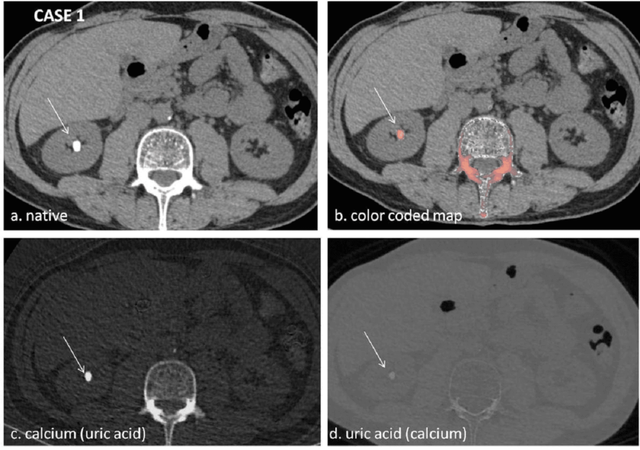

胆囊阴性结石通常小于3-4毫米,且在常规影像学检查中不易被发现。能谱CT通过其多能量成像(40-140keV)可显示病灶在不同能量下成像的特点,对于胆囊阴性结石而言,不同成分的结石在不同能量下的 X 线吸收和衰减特性有着独特的 “指纹”。通过对这些能谱数据的精准分析,能谱 CT 能够清晰地区分结石与周围的胆汁、软组织等结构。如下图所示,常规混合能量CT无法显示的胆囊结石,在40keV时成像低密度影,140keV时成像高密度影,与周围的胆汁对比显著,能够有效提高胆囊阴性结石的诊断准确性。

能谱CT多物质分离成像显示不同成分的结石